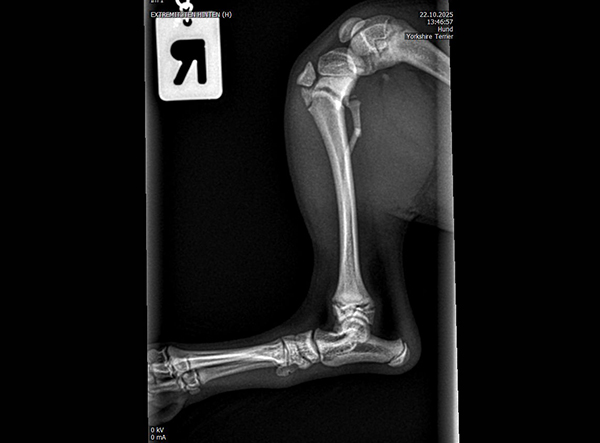

The patient, an 18-week-old female Yorkshire Terrier, was referred for surgery on October 21, 2025. The dog had sustained a fall from the owner’s arms, resulting in a fracture of the proximal tibial metaphysis just below the growth plate, along with a fibular fracture. Given the patient’s very small size and young age, precise anatomical fixation and minimal disruption of the growth zone were essential.

An open reduction and internal fixation (ORIF) was performed via a medial approach to the proximal tibia.Implant Used: 1.5 mm LeiLOX TPLO Swing Titanium Plate

The surgery was completed without complications. Postoperative radiographs confirmed anatomical alignment and stable fixation. With careful rehabilitation, the young Yorkshire Terrier is expected to regain full function and resume normal activity pain-free.